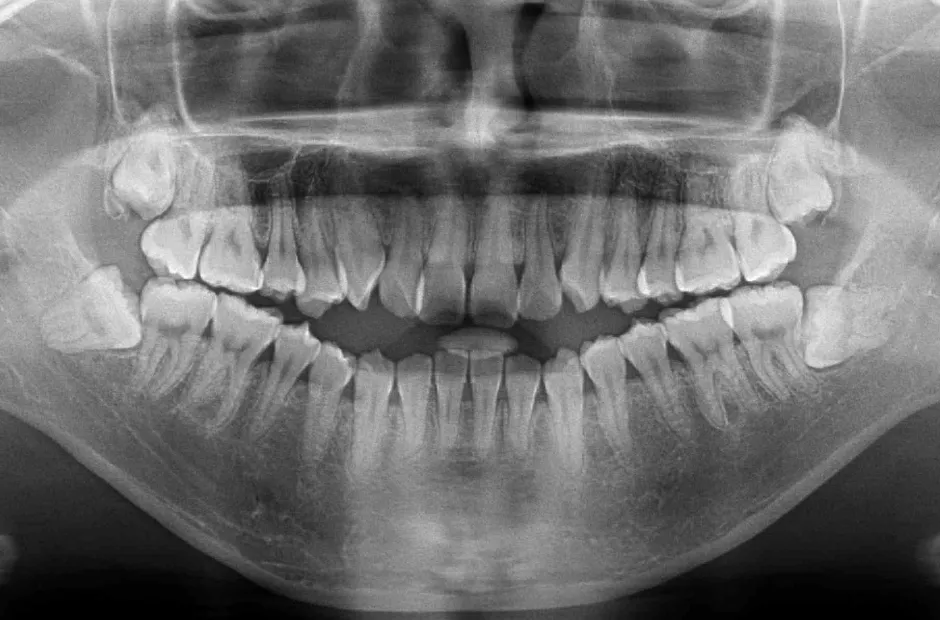

叢生

| 診断名・主訴 | 叢生 |

|---|---|

| 年齢・性別 | 43歳・女性 |

| 治療期間・回数 | 2年7か月 27回 |

| 治療に用いた主な装置 | 舌側矯正 |

| 抜歯部位 | 両顎4,4 |

| 治療費 | 100万円(税抜) |

| リスク・副作用 | 装置による違和感・疼痛・歯肉退縮・歯根吸収・虫歯のリスクなど |